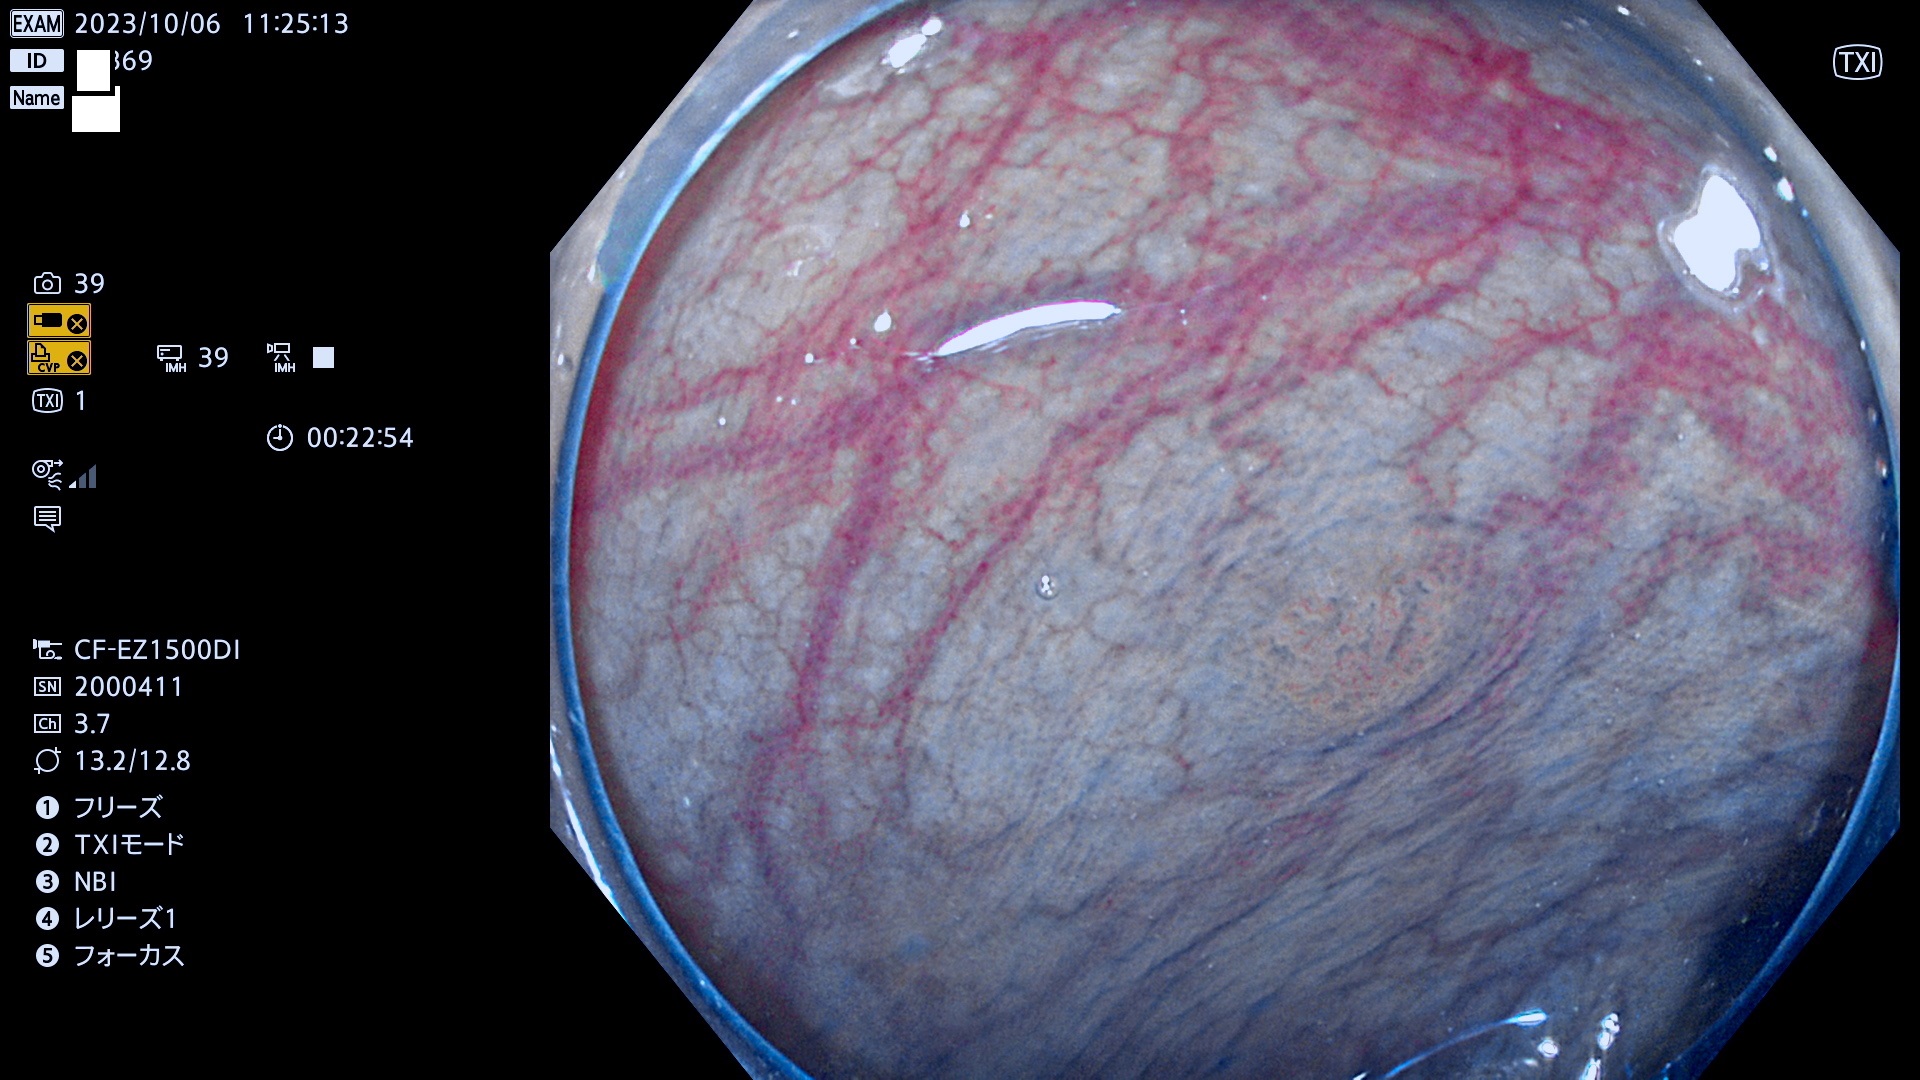

表面型腺腫(Flat Adenoma)の中で、完全に平坦な物をUb、陥凹している物をUcと呼びます。平坦隆起型(Ua)よりも、発見が難しく危険な病変です。このタイプは「内視鏡後・大腸癌の重要犯人」であり、この発見率は「腺腫発見率」よりも、重要な意味があります。

専門的)何故、陥凹していると危険? 癌遺伝子の変異が蓄積すると細胞分裂が盛んになり隆起するのでは?と通常は思われるでしょう。しかし実際は逆です。これは2022年の記事にある「細胞はストレスに直面したら細胞分裂を止める(細胞老化に入り休眠する)という生命の基本的現象」によるものです(Oncogene Stress)。細胞老化を起こすのが癌抑制遺伝子で、この安全装置(ブレーキ)が壊れると癌になります(休眠からの覚醒)。ですから陥凹は「まだ癌では無いが癌化の直前」を意味します。特に「小サイズなのに陥凹している」病変は短期間に腫瘍進化(⇒2021年記事)が起きたことを意味します(=ゲノム不安定性

専門的)Uc=De Novo癌? 内視鏡の解像度が低かった時代、このような説もありました。しかし今日の高精度内視鏡では良性の微小なUc型腺腫が日常的に見つかります。私見ですが「Ucこそが多段階発癌(Adenoma-Carcinoma Sequence)のMain Route」と考えます。

毎週の検査(木・金・土・日)に発見されたUb、Uc型・腺腫を、その週の日曜の夜にUPし1週間、提示します。

抽出の対象期間 2023年10月4日(木)〜10月9(月)の5日間(60件の検査)8件